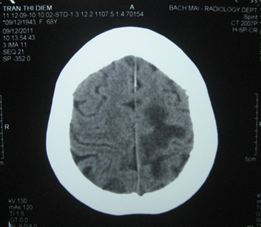

Chụp CT sọ não (9/12): Có u não ở vùng đỉnh trái, kích thước khoảng 1,8 cm, có phù não xung quanh khối u.

Hình 1: Hình ảnh chụp CT sọ não có u não ở vùng đỉnh trái, kích thước khoảng 1,8 cm, có phù não xung quanh khối u